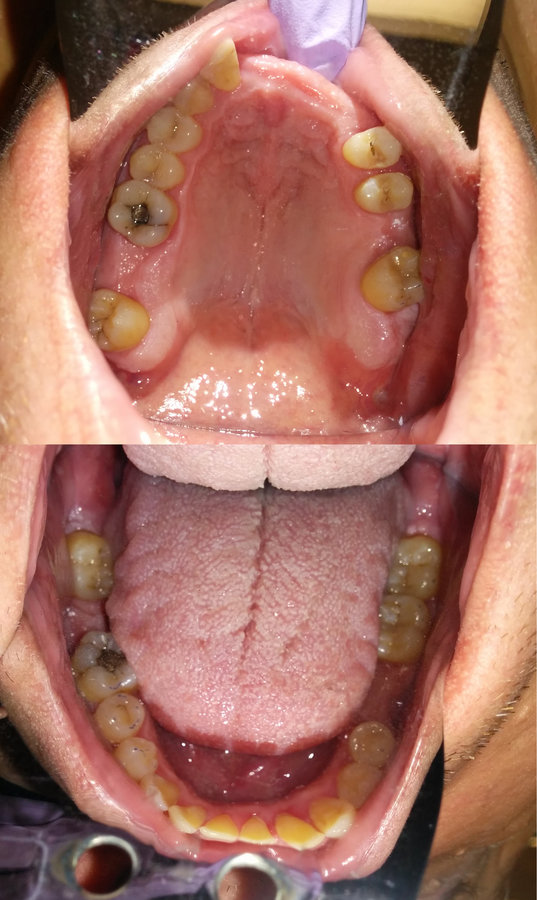

Perio charting and Odontogram

- Orthodontics/Prosthodontics: Pt. has Class III Occlusion and missing #2, 8, 9, 10, 11, 14, 19 and 31

Stage 1: Educate and Clean

- Full mouth SRP

- Periodontal Re-evaluation (4-6 weeks post-SRP)